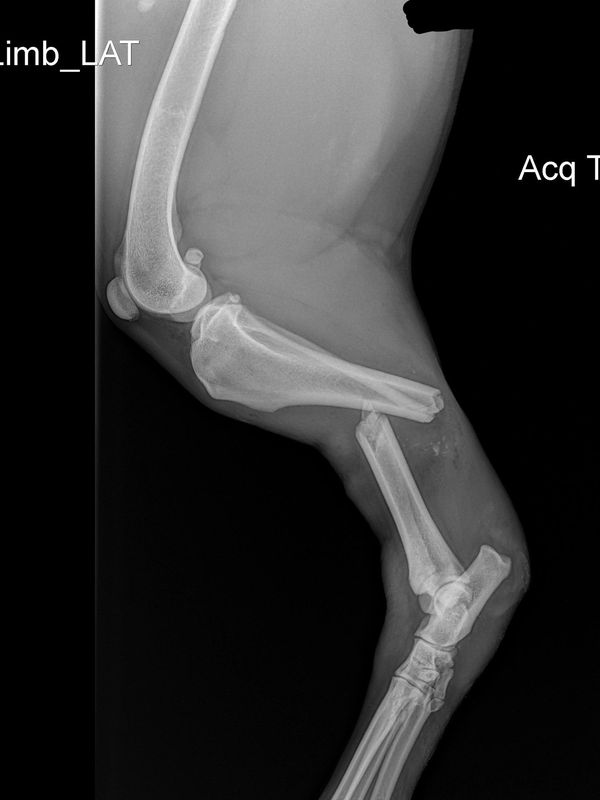

This x-ray was taken prior to surgery. You can see a fracture in the tibia and fibula of the left leg.